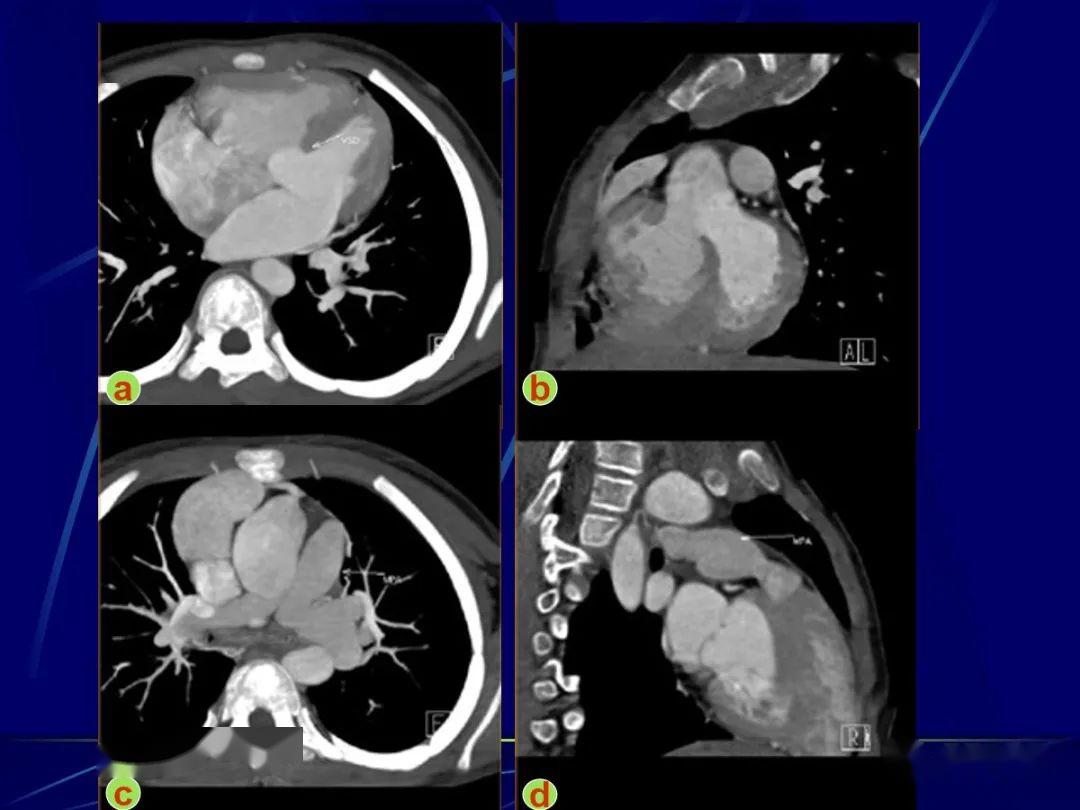

从ct图来看, 其心包积液的量属于轻度,中度,重度? 4

胸痛三天,加重三小时(ct是心包高密度影是什么) [病例帖]